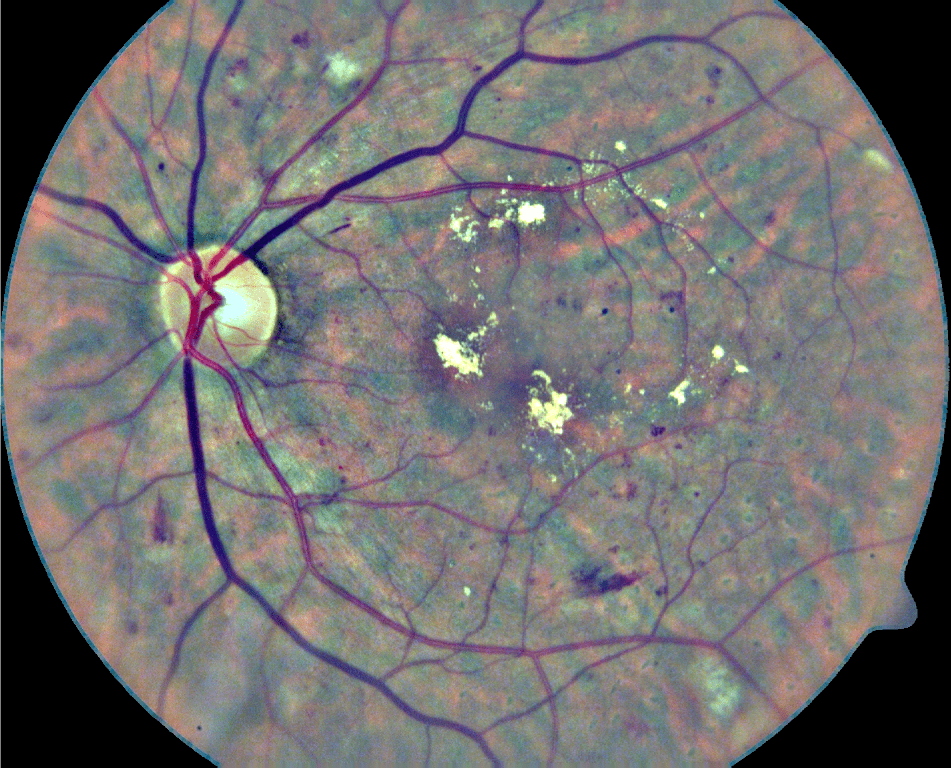

In its early stages, DR might be clinically asymptomatic (Abràmoff et al., 2010). As a consequence, this condition is typically identified when it is more advanced and treatments are significantly less effective (Mookiah et al., 2013). A recent study has shown that 44% of hospitalized patients with diabetes remain undiagnosed (Kovarik et al., 2016). To prevent this, people suffering from diabetes are usually recommended to be regularly examined through fundus images to verify the non-existence of red lesions (Abràmoff et al., 2010). Although fundus photographs are currently the most economical non-invasive imaging technique for this purpose, manual diagnosis requires an intensive effort to screen the images (Mookiah et al., 2013). Red lesions appear as small red dots that might be subtle and too small to be detected at first glance (Figure 1). Large HEs, on the contrary, are more evident and less difficult to visualize.

Refer to caption

Figure 1: Examples of red lesions observed in fundus photographs from DIARETDB1 (Kauppi et al., 2007).